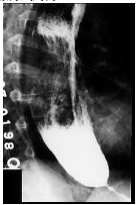

73 78 歲張三老先生因為咳嗽多痰、胸悶而到醫院求診。醫師診察後為他做胸部 X 光照相,發現縱膈腔 異常,進而做上消化道鋇劑 X 光攝影。胃和食道情況如下圖所示。則張老先生最有可能罹患: (A)食道裂孔胃疝氣(hiatal hernia of stomach) (B)食道重複(esophageal duplication) (C)胃靜脈曲張(gastric varices) (D)食道靜脈曲張(esophageal varices)